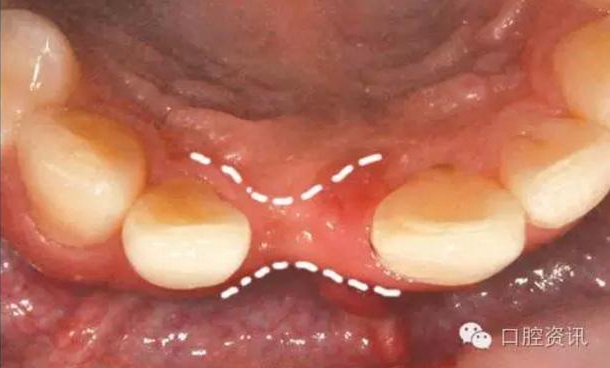

11.jpg

圖11. 拔牙后出現(xiàn)牙床萎縮